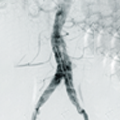

Hercules®/定海杵™分叉型覆膜支架及输送系统

Hercules®/定海杵™分叉型覆膜支架及输送系统主要用于腹主动脉瘤的介入治疗。适用于近端瘤颈大于15mm的肾下型腹主动脉瘤。